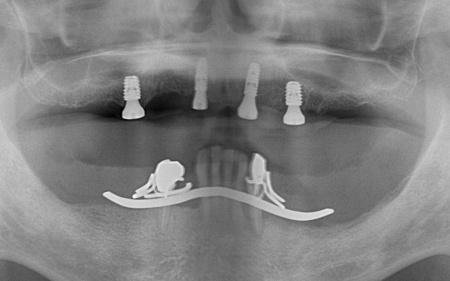

60代男性 破損した上下の入れ歯を作り直して噛み合わせを改善した症例

- インプラント

- 入れ歯・義歯

- 抜歯

- 治療期間の目安 約8ヶ月

- 治療費総額の目安 約1,300,000円

・持病をお持ちの方や、服用中のお薬の種類によっては、外科処置ができない場合があります ・メンテナンスを怠ったり、喫煙したりすると、お口の中に大きな悪影響を及ぼし、インプラント周囲炎などにかかる可能性があります ・糖尿病、肝硬変、心臓病などの持病をお持ちの場合、インプラント治療ができない可能性があ...